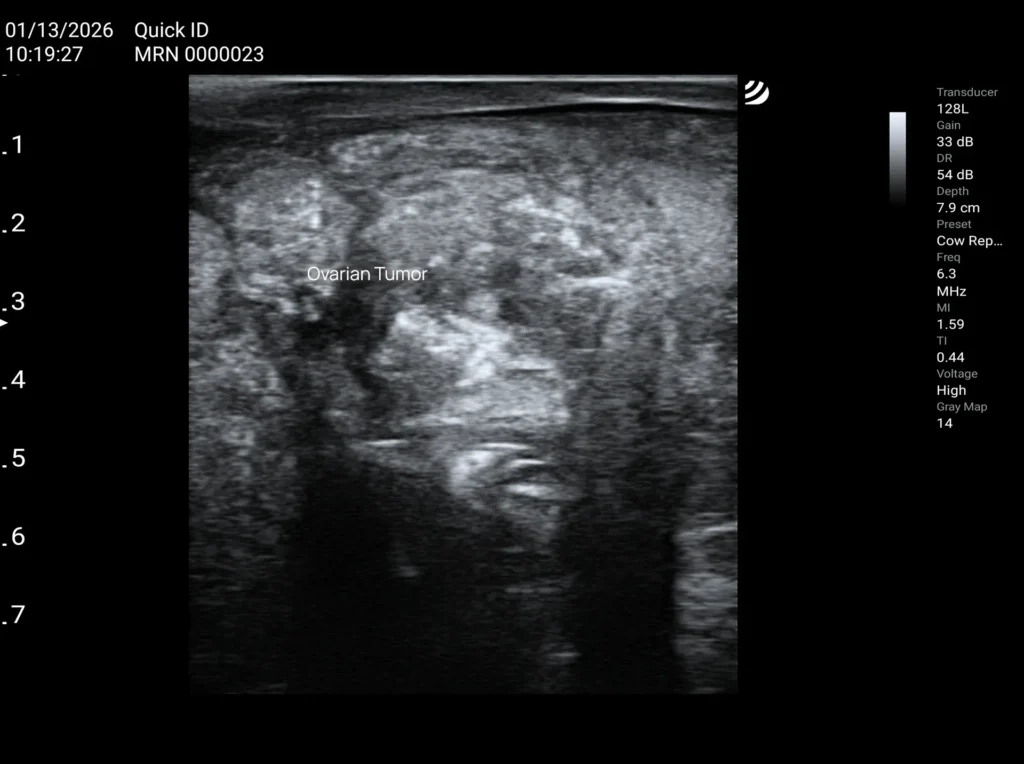

Ovarian and Uterine Tumors in Cows

Ovarian Granulosa Cell Tumor

Most often detected during a per rectum examination, usually only once it has reached a considerable size and causes noticeable deformation of the ovary.